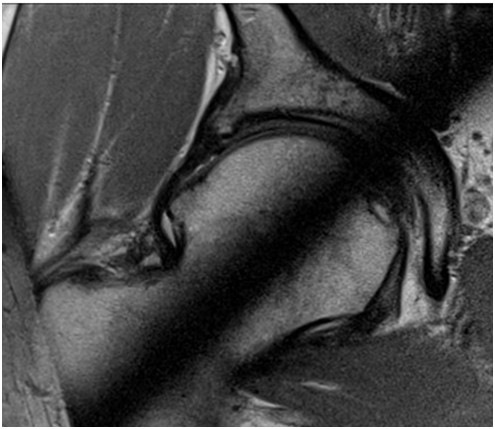

32-letni mężczyzna odczuwa ból biodra prawego. Dotychczas dość intensywnie uprawiał sporty walki. Klinicznie: stwierdza się ograniczony bólem zakres ruchów, z pomniejszeniem zgięcia, przywiedzenia i rotacji wewnętrznej. Na podstawie obrazu przekroju osiowego stawu biodrowego, na przekroju zegarowym 12:00 - 6:00, wskaż właściwe postępowanie lecznicze:

Pytanie 107